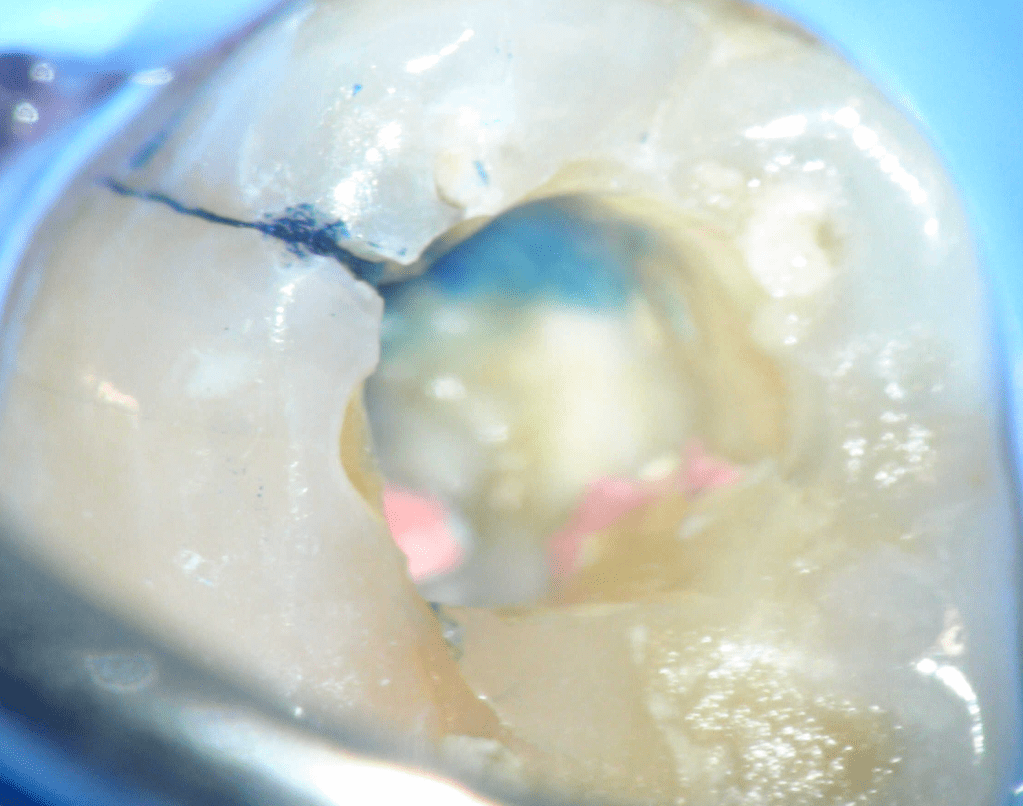

Fisura, remoción amalgama para explorar